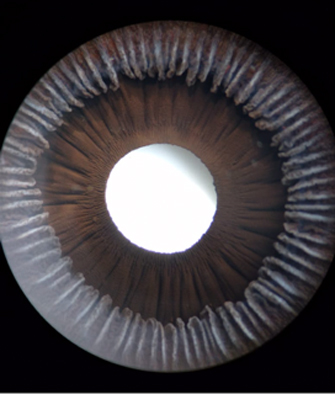

En la cara Posterior se ven pliegues radiales muy finos que se extienden desde el margen pupilar hasta el collarete ( miden ± 1.0 mm), y son conocidos como Pliegues radiales de contracción de Schwalbe. Existen ademas los llamados Pliegues estructurales de Schwalbe que son mas gruesos y mas distanciados en la porción ciliar de la cara posterior

Cara posterior de Iris: incluye Iris y Cuerpo Ciliar, Foto tomada de globo ocular de banco de ojos.